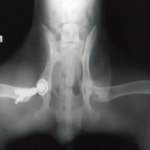

症例1 ゴールデン・レトリバー 7歳 避妊雌

後肢の跛行を主訴に来院されました。レントゲン検査にて、左右股関節の形成不全および重度の関節炎所見を認めました。THRに関しては適応年齢(約9カ月齢以降)の範囲にありますが、左右とも長期に及ぶ骨関節炎の進行により、大腿骨頭・寛骨臼ともに重度の骨変形を伴っていました。このような症例において、THRのカップの定着が悪くTHRの手術の成功率が下がるため、機能回復の面では劣りますが、症状がより重いと判断された左後肢の大腿骨頭・骨頚切除術を実施しました。今後は、リハビリテーションを行い、患肢の機能回復に努めると共に、反対側の大腿骨頭・骨頚切除術を検討していく予定です。

股関節形成不全は成長期に発症する進行性の関節疾患です。若齢期でのTHRの選択が機能回復において最も優れています。好発犬種のワンちゃんは成長期からの定期的な股関節のレントゲン検査をお勧めいたします。(詳しくは上記の診断を参照してください。)

術前レントゲン

術後レントゲン